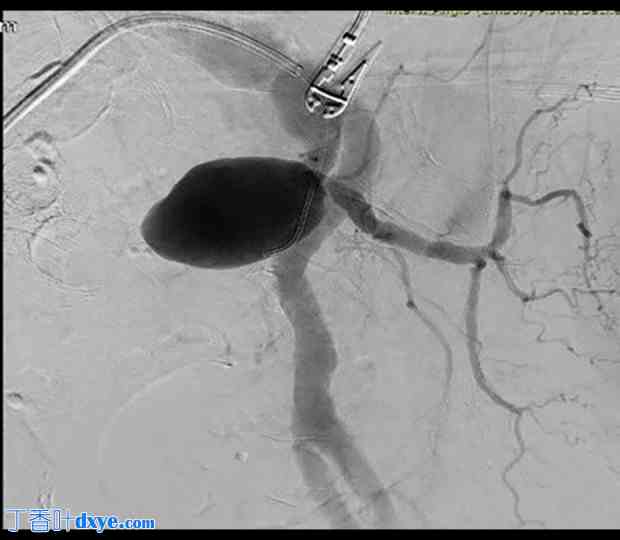

2024年8月初,患者因严重下消化道出血导致休克,入院急诊科。初步影像学检查,包括腹部CTA,显示左侧髂内动脉瘤显著增大,直径达61 mm(图1),并可见动脉瘤与乙状结肠之间存在瘘管,该瘘管被认为是消化道出血的来源。由于动脉瘤囊内有气体,且邻近区域有积液,提示存在感染,因此怀疑该动脉瘤为真菌性。此外,还发现左侧输尿管受压,导致尿流受阻。

图1.

计算机断层扫描血管造影显示髂内动脉瘤,最大直径为61 mm(绿色箭头)。